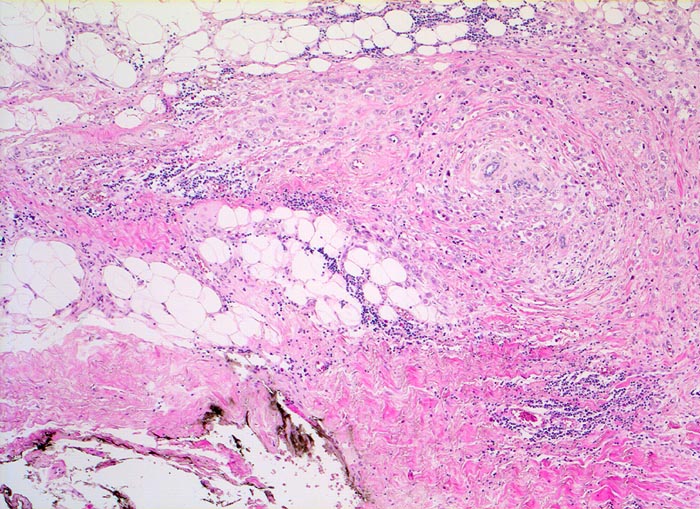

PathoPic – image database / PathoPic ID 5243 - Invasives lobuläres Mammakarzinom

Invasives lobuläres Mammakarzinom

Die Tumorzellen sind konzentrisch um vorbestehende Läppchen angeordnet. Der Tumor reicht hier bis nahe an den mit schwarzer Tusche markierten Resektionsrand heran.

Mammographisch suspekter Herd im äusseren oberen Quadranten. Probeexzision.

Damit der Pathologe den Abstand des Tumors von den verschiedenen Resektionsrändern bestimmen kann, werden diese mit verschieden farbiger Tusche markiert